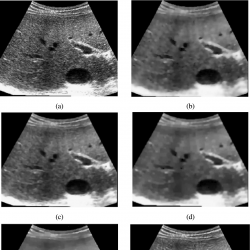

Fig. 7

Visual comparison of various speckle suppressing methods on a ultrasound image of a tumour. (a) Original image. (b) The denoising result using SRAD (Yu and Acton,

2002). (c) The result using VO method (Vese and Osher,

2003). (d) The denoised result using framelet regularization method without backward diffusion (Wang

et al.,

2014). (e) The denoised result using framelet regularization method and backward diffusion (Wang

2014). (f) The result of the proposed method.

2014), we employed the proposed method to two real noisy medical ultrasound images (see Figs.

5(b) and

5(c) same as in Yu and Acton (

2002), Vese and Osher (

2003), Wang

et al. (

2014)). The results of our proposed method in comparison with the results of state-of-the-art methods mentioned in Yu and Acton (

2014) are listed in Figs.

7 and

8.